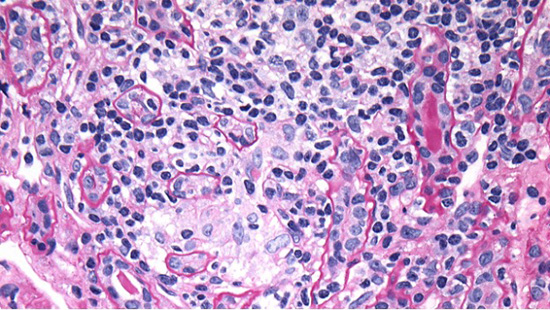

Light microscopy (LM) shows renal cortical inflammation composed of lymphocytes and macrophages with few eosinophils and plasma cells (Fig. 1A). Mature and evolving tubular atrophy and interstitial fibrosis are in much of the cortex, with inflammation in predominantly proximal and atrophied tubules (Fig. 1B). Preserved tubules have epithelial cell acute injury. There is no medullary inflammation. LM of the immunofluorescence (IF) and electron microscopy (EM) specimens shows unremarkable glomeruli (Fig. 2A).

Figure 1A. Light microscopy - (A) H&E stain showing cortical interstitial inflammation composed of lymphocytes and macrophages with few eosinophils and plasma cells (inset).